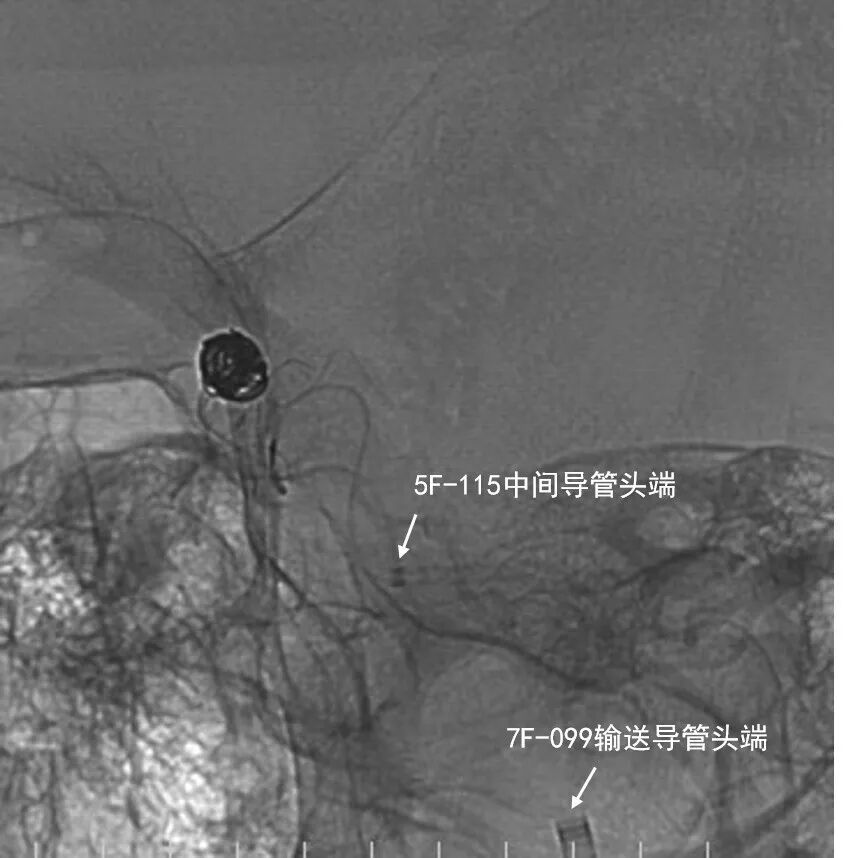

- 5F 115cm颅内支持导管在泥鳅导丝支撑下超选入右侧颈内动脉C3段内。支架微导管先经5F颅内支持导管在微导丝支撑下超选入右侧大脑中动脉M1段。后微导管塑形后经深瑞达7F 90cm输送导管在微导丝支撑下超选入动脉瘤腔内。

动脉长鞘怎么置入深谋远路 | 千人皆翘首,万唤今始来——国内首款7F长鞘在血流导向密网支架联合弹簧圈栓塞治疗动脉瘤的首次应用_https://www.jmylbn.com_新闻资讯_第25张

微导管后撤弹入瘤腔

路图下先释放4.0*25mm 密网支架完全覆盖瘤颈,用J型微导丝予以支架内按摩。术中 Vaso CT证实支架打开贴壁良好。

动脉长鞘怎么置入深谋远路 | 千人皆翘首,万唤今始来——国内首款7F长鞘在血流导向密网支架联合弹簧圈栓塞治疗动脉瘤的首次应用_https://www.jmylbn.com_新闻资讯_第26张

Vaso CT证实支架打开贴壁良好